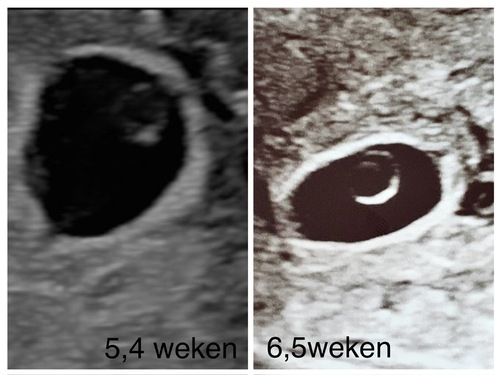

Met dit termijn moet je wel een hartje zien kloppen of zien dat het is gegroeid. Ik vond het ook heel onwerkelijk maar in het ZKH maken ze sowieso nog een echo en leggen ze precies uit wat ze zien.. t is ook wel echt heel moeilijk te geloven want je hormonen gieren door je lijf